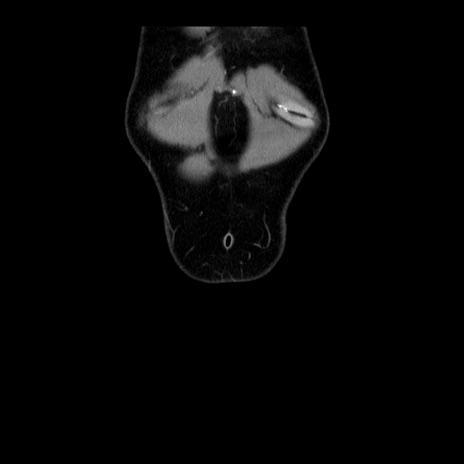

症例4(冠状断像)

横断像